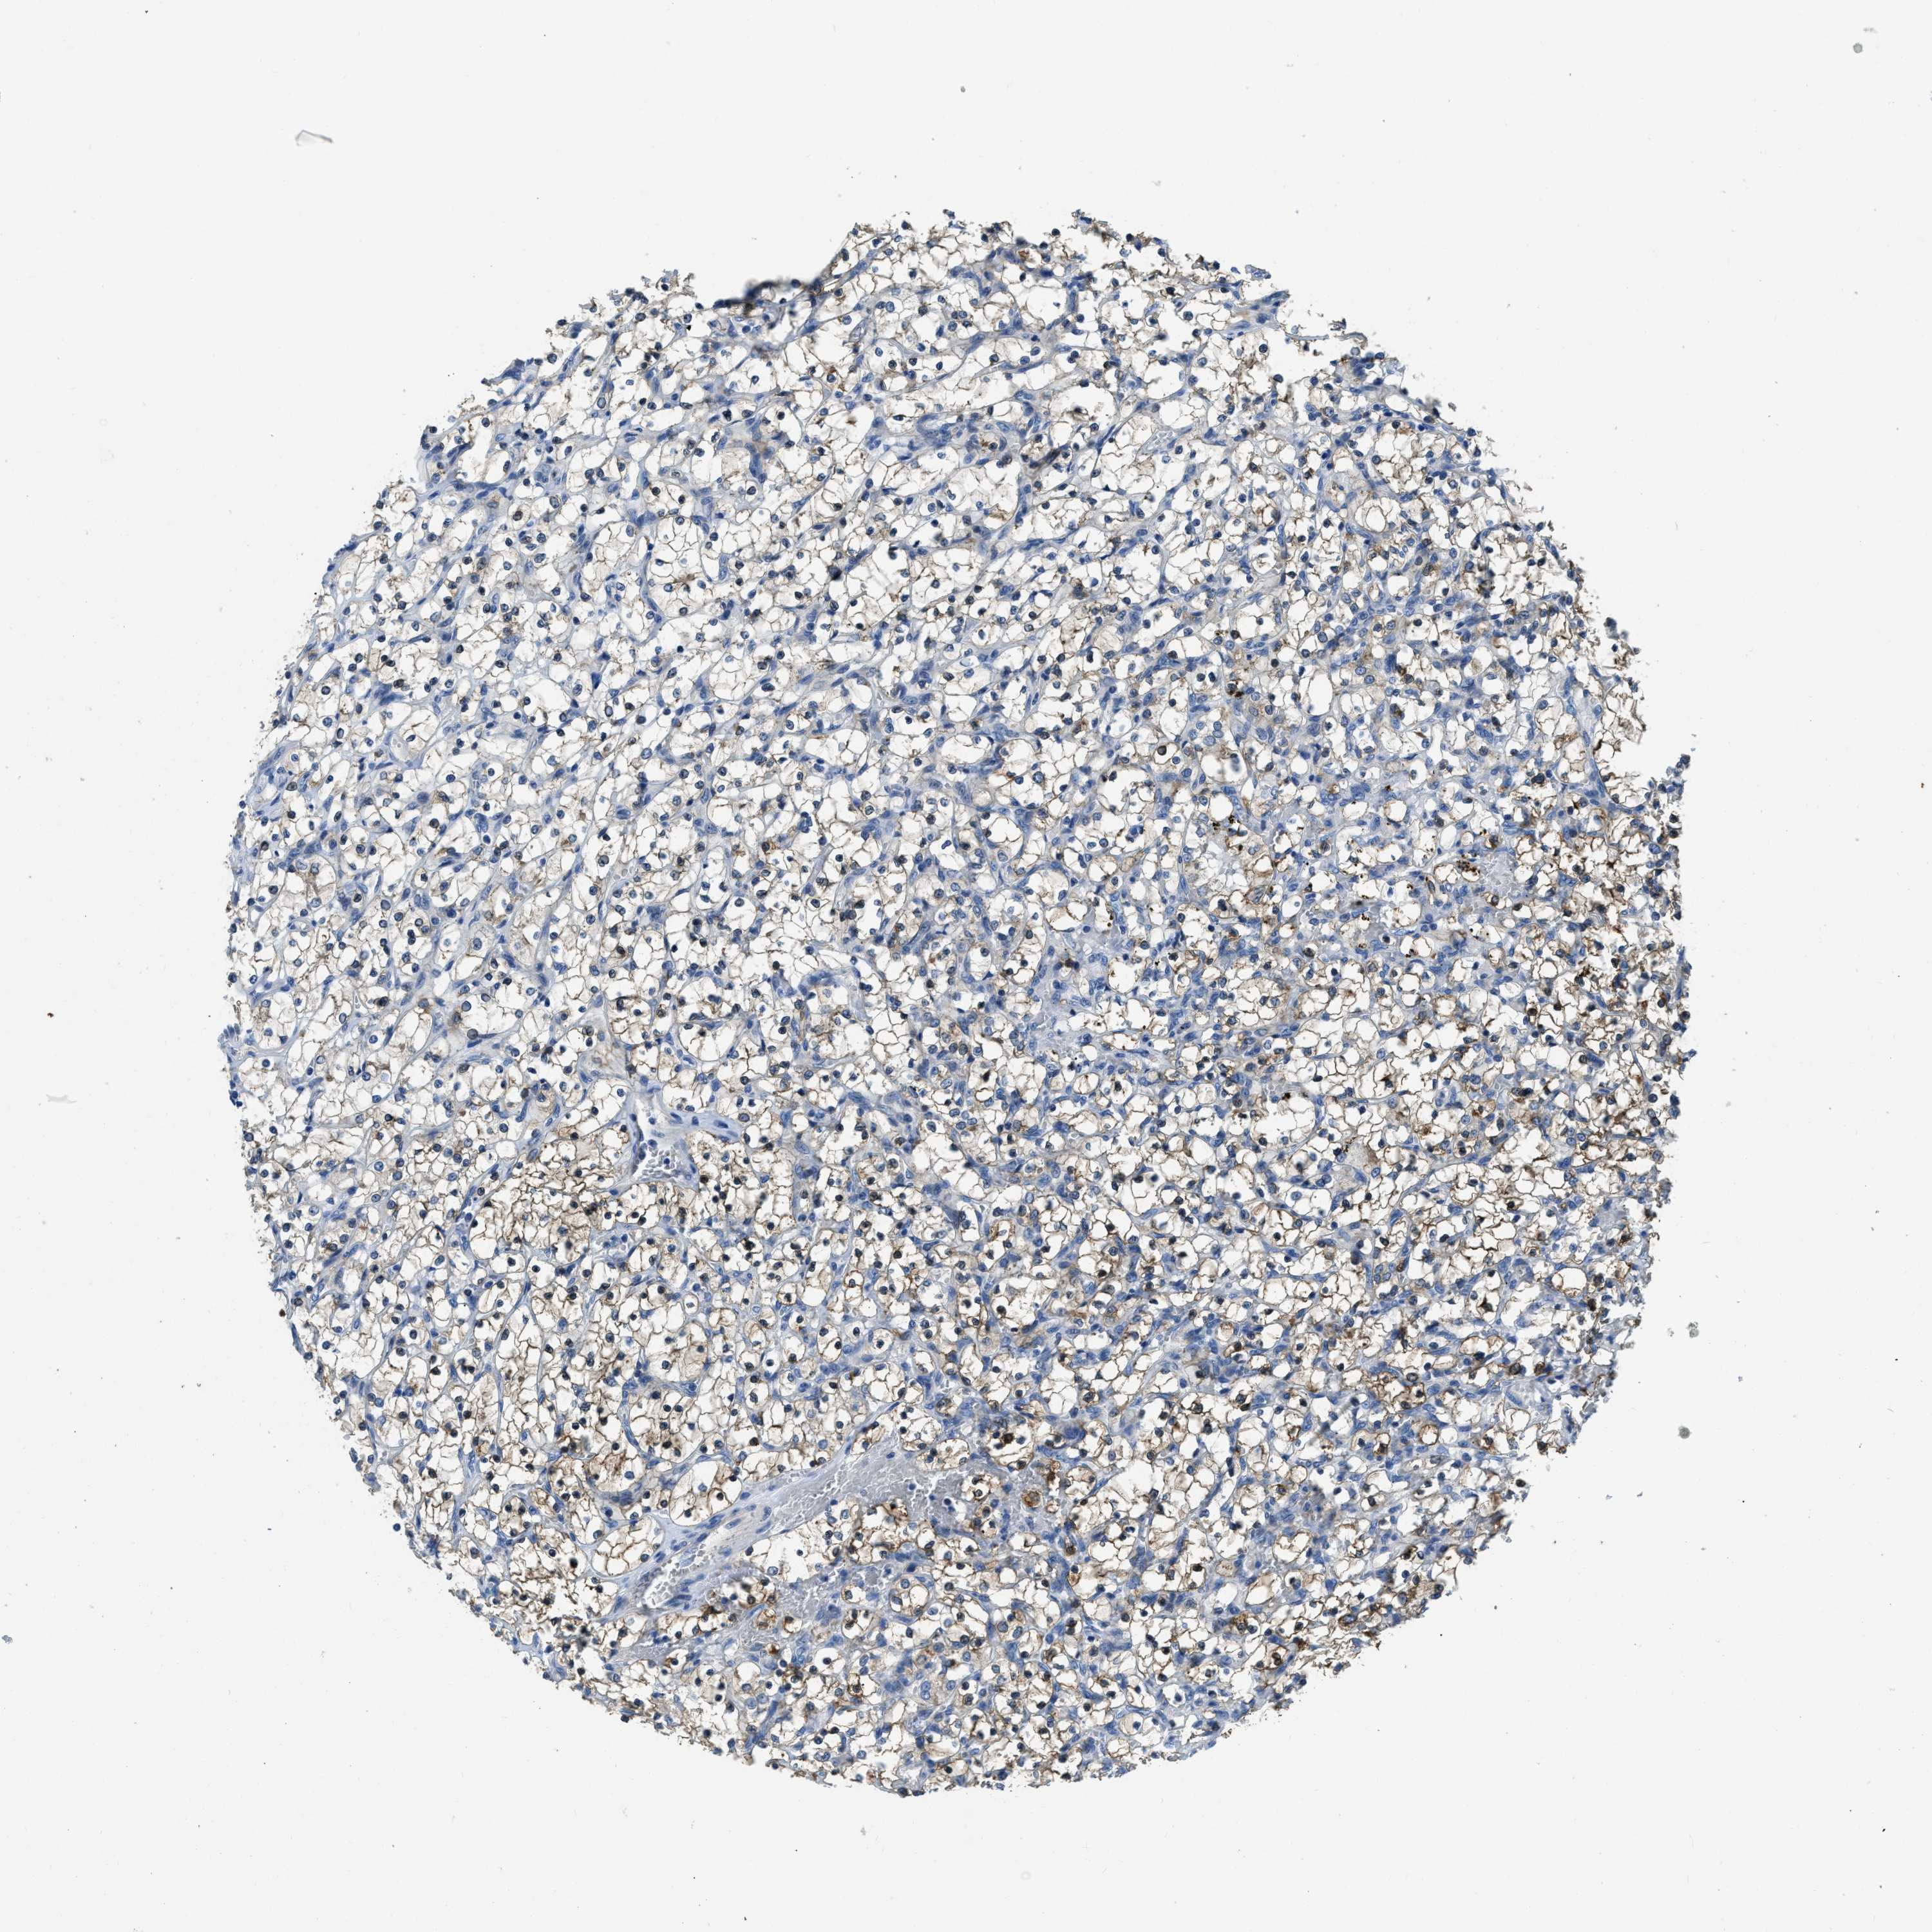

KIDNEY RENAL CLEAR CELL CARCINOMA (VALIDATION) - Interactive survival scatter ploti

The Survival Scatter plot shows the clinical status (i.e. dead or alive) for all individuals in the patient cohort, based on the same data that underlies the corresponding Kaplan-Meier plots. Patients that are alive at last time for follow-up are shown in blue and patients who have died during the study are shown in red.

The x-axis shows the expression levels (FPKM) of the investigated gene in the tumor tissue at the time of diagnosis. The y-axis shows the follow-up time after diagnosis (years). Both axes are complimented with kernel density curves demonstrating the data density over the axes. The top density plot shows the expression levels (FPKM) distribution among dead (red) and alive patients (blue). The right density plot shows the data density of the survived years of dead patients with high and low expression levels respectively, stratified using the cutoff indicated by the vertical dashed line through the Survival Scatter plot. This cutoff is automatically defined based on the FPKM cutoff that minimizes the p-score. The cutoff can be changed by dragging the vertical line or by entering a cutoff value in the square labeled "Current cut-off".

Under the Survival Scatter plot the p-score landscape (black curve; left axis) is shown together with dead median separation (red curve; right axis). Dead median separation is the difference in median mRNA expression between patients who have died with high and low expression, respectively. It is calculated as follows: median FPKM expression of dead patients with high expression - median FPKM expression of dead patients with low expression. This is intended to aid the user in visually exploring custom cutoffs and the associated p-scores and dead median separation.

Individual patient data is displayed and can be filtered by clicking on one or more of the category buttons on the top of the page. Categories describing expression level and patient information include: high, low, alive, dead, female, male and tumor stages. The scale of the x-axis can be toggled between linear and log-scale by clicking on the "x log" button. Mouse-over function shows TCGA ID, patient information and mRNA expression (FPKM) for each patient.

& Survival analysisi

Kaplan-Meier plots summarize results from analysis of correlation between mRNA expression level and patient survival. Patients were divided based on level of expression into one of the two groups "low" (under cut off) or "high" (over cut off). X-axis shows time for survival (years) and y-axis shows the probability of survival, where 1.0 corresponds to 100 percent.

PFKP is not prognostic in Kidney Renal Clear Cell Carcinoma (validation)

Best expression cut offi

Based on the FPKM value of each gene, patients were classified into two groups and association between prognosis (survival) and gene expression (FPKM) was examined. The best expression cut-off refers the FPKM value that yields maximal difference with regard to survival between the two groups at the lowest log-rank P-value. Best expression cut-off was selected based on survival analysis .

When clicking on this number, the vertical dashed line indicating cut-off, the interactive survival plot, and the Kaplan-Meier curve will be adjusted to show results based on the best expression cut-off.

: 255.83

Average pTPM 368.7

Number of samples 100